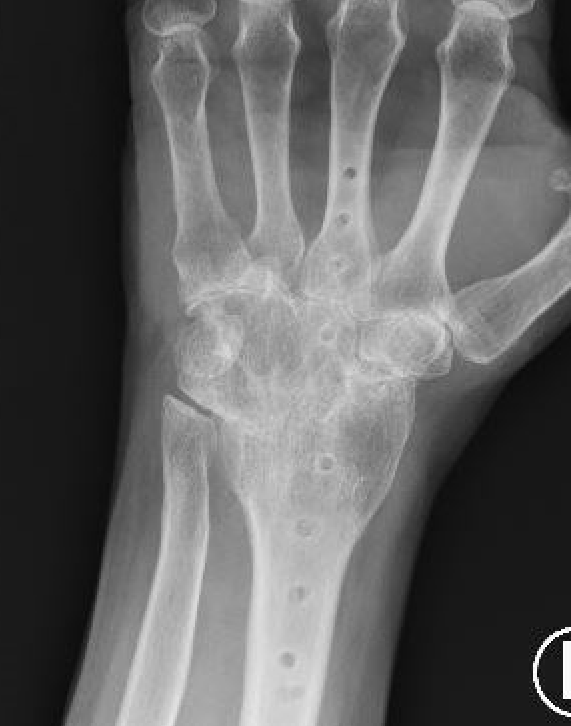

Spanning dorsal plate

Concept

Distal radius to third metacarpal

- fusion radiocarpal & midcarpal +/- fusion of 3rd carpometacarpal joint

- low profile and precontoured plate

- 15 degree dorsal angulation and slight ulna deviation to maximize grip strength

Non spanning dorsal plate

Sparing 3rd carpo-metacarpal joint